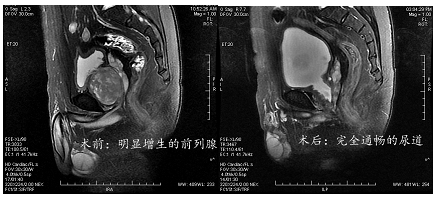

B超在前列腺癌筛查中的作用在大型三甲医院,B超可通过观察前列腺外周带是否存在低回声信号,初步判断是否存在癌变风险低回声信号是前列腺癌的典型超声表现之一,若发现此类异常,医生会高度怀疑前列腺癌,但需进一步检查确认确诊需依赖病理检查B超仅能提供形态学线索,真正确诊前列腺癌需通过B超引导下的;前列腺常规检查的目的和意义主要体现在以下几个方面一初步筛查前列腺疾病通过直肠指诊,医生可直接触摸前列腺,感知其形态大小及硬度,初步判断是否存在炎症增生或肿瘤例如,前列腺质地变硬或表面不规则可能提示癌变风险,而触痛或肿胀则可能与炎症相关这一检查是前列腺疾病筛查的基础手段,操作;第四,周围组织关系B超还能评估前列腺与膀胱直肠等邻近器官的关系,判断是否存在压迫或浸润例如,前列腺增生可能压迫尿道导致膀胱残余尿量增加,而肿瘤侵犯周围组织时可能显示边界模糊或结构紊乱临床意义前列腺B超作为无创经济的影像学检查,是前列腺疾病筛查和诊断的重要手段它不仅能发现结构异常,还可为后续治疗如药物干预手术提供形态学依据但需注意,B超结果需结合临;通过前列腺B超,医生可以测量前列腺的大小,判断其是否在正常范围内同时,还能观察前列腺内部是否存在异常情况,例如是否有钙化灶钙化灶的出现可能与前列腺的慢性炎症损伤修复等过程有关,对于诊断某些前列腺疾病具有一定的参考价值不过,前列腺B超也存在一定的局限性在诊断前列腺炎症和前列腺肿瘤方;检查意义前列腺B超能发现多种前列腺病变,包括前列腺增生导致排尿困难结节可能提示肿瘤或炎症囊肿良性液性包块等此外,它对前列腺癌的诊断具有辅助价值,可通过观察前列腺形态血流信号等特征提供线索医生还可通过B超评估前列腺功能,如残余尿量膀胱排空情况等,为治疗方案的制定提;若PSA水平异常升高,需结合直肠指诊B超或磁共振成像MRI进一步排查前列腺癌需注意,PSA升高也可能由良性前列腺增生或炎症引起,需综合判断临床意义上述检查项目覆盖炎症增生及肿瘤等前列腺常见疾病,医生会根据患者症状年龄及初步检查结果选择针对性检查,以实现精准诊断和个体化治疗;需注意的局限性前列腺B超无法单独确诊疾病,需结合PSA检测直肠指诊或MRI等综合判断例如,PSA升高可能提示前列腺癌,但需通过B超定位病灶后进一步活检确认特殊人群的注意事项老年男性前列腺疾病高发,B超是常规筛查手段年轻男性若存在高危因素如家族史,需结合其他检查生活方式久坐高。

特殊人群注意事项儿童前列腺较小,B超诊断价值有限,通常依赖其他检查孕妇需告知医生怀孕情况,医生会选择安全检查方式前列腺疾病患者检查前尽量排空膀胱以获得清晰图像若服用抗凝药物,需提前告知医生以规避风险前列腺B超是筛查前列腺疾病的重要手段,但最终诊断需结合临床症状与其他检查出现;前列腺B超能检查出什么 前列腺B超即采用B型超声波对前列腺进行检查临床用于测定前列腺的形态大小及位置,可用于诊断前列腺增生前列腺肿瘤结石钙化等症以及前列腺脓肿囊肿及慢性前列腺炎,也可用于探测前列腺尿道合金支架管的位置适应于怀疑患有前列腺增疾病的病人,也常用于健康男性的体检;确诊前列腺癌通常需要进行前列腺特异性抗原PSA检测直肠指检前列腺穿刺活检等一系列检查而且,由于前列腺体积小,彩超在成像上标示腺体出血管的分布等情况时,会影响对病灶体积和硬度的判断,不如B超在观察腺体病灶方面直接和清晰需要强调的是,虽然彩超有上述潜在辅助作用,但在前列腺疾病检查中;前列腺B超能检查出以下内容一前列腺的大小形态和结构通过B超可测量前列腺的长宽厚,判断其整体形态是否异常,如是否存在增生肥大或结节等改变例如,前列腺体积增大可能提示良性前列腺增生,而局部结节需警惕肿瘤风险二前列腺内的回声情况正常前列腺回声均匀,B超可检测异常回声区域结石;相关人群B超检查前列腺炎的注意事项成年男性检查前需适度充盈膀胱,使前列腺显示更清晰,避免膀胱充盈不足影响结果准确性,同时要放松心情,避免紧张导致前列腺部位肌肉紧张,影响B超图像获取老年男性本身可能合并前列腺增生等其他前列腺疾病,检查时更要注意结合其他检查手段全面评估,防止漏诊或误诊儿童。

前列腺B超能够检查出以下内容1前列腺大小通过测量前列腺的长宽厚等尺寸,判断其是否增大或缩小正常前列腺大小因人而异,但前列腺增生前列腺炎等疾病可能导致体积增大例如,前列腺增生患者的前列腺可能明显超过正常范围,提示疾病风险2前列腺形态B超可观察前列腺形态是否规则,是否存在结节。

值得注意的是,这项检查可能对某些患者来说会引起不适,尤其是对于那些对直肠检查有顾虑的人如果患者感到不适,应该及时告知医生在某些情况下,医生可能会使用局部麻醉来减轻不适感前列腺B超检查是一项无创的检查方法,对于诊断前列腺疾病具有重要意义通过这项检查,医生可以更好地了解前列腺的情况;1 前列腺肥大增生前列腺B超可清晰显示前列腺的形态大小及内部结构,通过测量其长宽厚等参数,判断是否存在体积增大即前列腺增生这是中老年男性常见疾病,B超检查可辅助评估增生程度及对尿道的压迫情况,为治疗提供依据2 前列腺钙化或包块B超能发现前列腺内的强回声光斑钙化灶;接下来对以上项目进行详细解释1 前列腺检查 前列腺是男性重要的生殖器官之一,B超检查可以帮助医生了解前列腺的大小形态和有无异常回声这种检查方法对于诊断前列腺炎前列腺增生等疾病具有重要的参考价值2 睾丸检查 睾丸是男性生殖系统的重要组成部分,通过B超检查可以观察睾丸的形态大小以及是否。